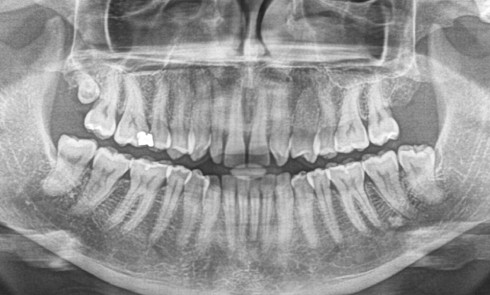

Les agénésies sont un motif de consultation fréquent des patients avec une prévalence de 4,6 % pour les hommes et...